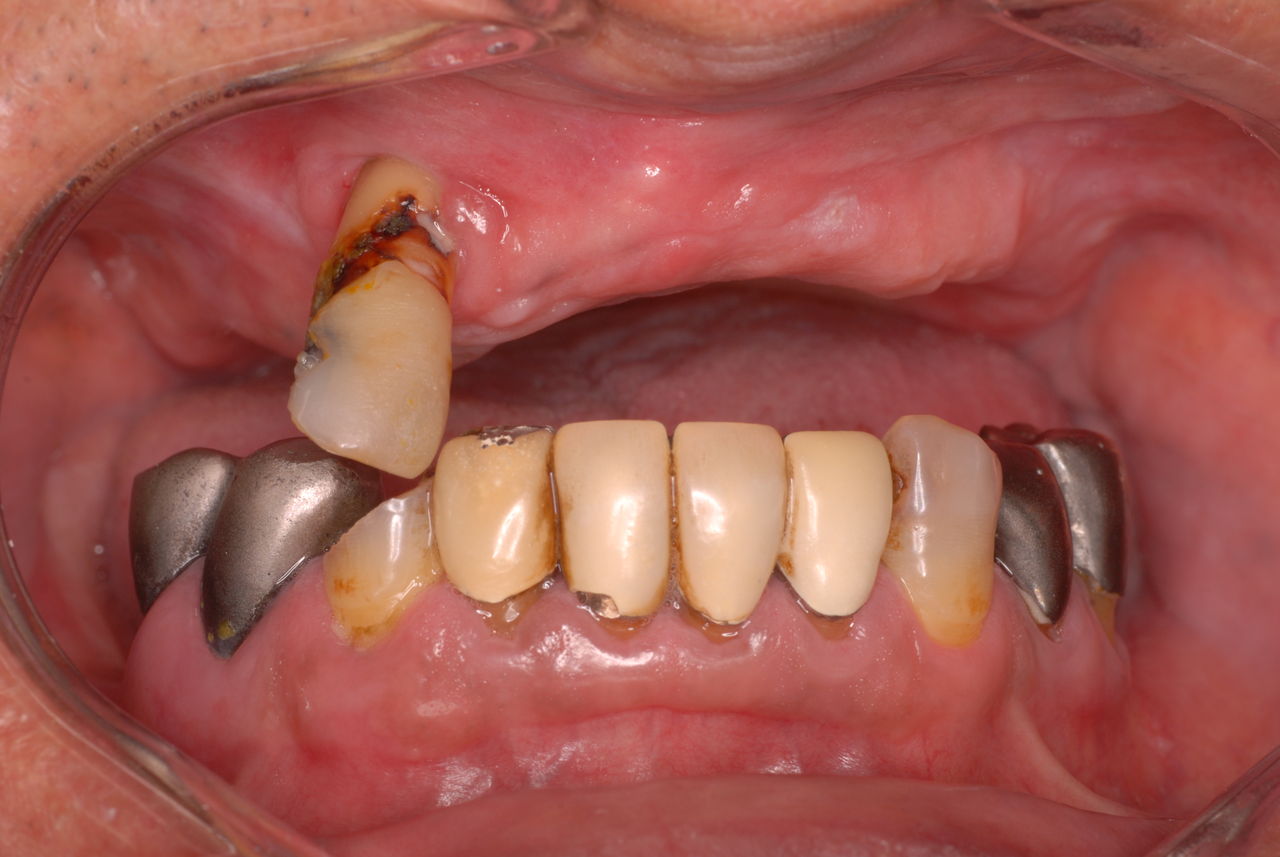

所が、見た目も悪くこれでどうやって人と会っていたのか、食べていたのか皆目想像できない方でした。

カビか何かが入り込んでいる異様な入れ歯でした。

上の歯は一本がブラブラでしたね。

上の総義歯はまっったくはずれませんでした。下顎の入れ歯では若干痛みが出そうなので噛み合わせの調整をしています。口腔内では時間がかかりすぎるので器械に付けて調整しています。

下顎が右にシフトしているので噛み合わせはとても慎重にしました。下の方が頬側にないと安定せず噛めないのです。

左側の噛み合わせはまともにできます。